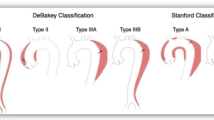

In clinical practice, the location and management of aortic dissection form the basis of its classification.15 Aortic dissection has been categorized by Stanford and DeBakey (Fig. 2).15,16 The Stanford classification is based on the location of the false lumen: Type A involving at least the ascending aorta and Type B referring to disease confined to the descending aorta beginning at the left subclavian artery.15 There are three categories in the DeBakey classification: 1) In DeBakey I, the false lumen extends from the ascending aorta to the descending aorta; 2) In DeBakey II, the false lumen was originally confined to the ascending aorta, but this category has now been modified to include disease in the aortic arch;16 and 3) In DeBakey III, as in Stanford Type B, the false lumen is confined to the descending aorta distal to the left subclavian artery. These classifications are useful for guiding requirement for surgery or conservative management: Stanford Type A or DeBakey I and II dissections require immediate surgical management, whereas Stanford Type B or DeBakey III aortic dissection may be managed conservatively or by endovascular stenting.17

Stanford, DeBakey, and Penn classification schemes for aortic dissection. In the Penn classification, Stanford Type A aortic dissection is integrated with DeBakey I (with descending aortic involvement) and DeBakey II (without descending aortic involvement). Similarly, for Stanford Type B aortic dissection, extension in the descending aortic may be in the thorax alone (DeBakey III extent A) or in both the thorax and abdomen (DeBakey III extent B). Further categorization is based on extension of clinical presentation with the following ischemic profile: a- absence of ischemia; b- branch vessel malperfusion; c- circulatory collapse; b and c- both branch vessel malperfusion and circulatory collapse. Within Stanford Type B or DeBakey III, Penn class a category may be subdivided into high risk (Type I) or low risk (Type II) of complications depending on the echo-anatomic features

Additional classification

A novel framework has recently been created for grading presenting features as well as prognosis and perioperative management (Fig. 2). This Penn classification (from the University of Pennsylvania) stratifies Stanford Type A aortic dissection into the presence (DeBakey I) or absence (DeBakey II) of descending thoracic aortic involvement.40 Similarly, for Stanford Type B aortic dissection, extension in the descending aortic may be in the thorax alone (DeBakey III a) or in both the thorax and abdomen (DeBakey III b).41 Each permutation is then divided into four categories according to branch vessel disease and circulatory dysfunction: Class a–aortic dissection with absence of branch vessel malperfusion or circulatory collapse (no end-organ ischemia); Class b–aortic dissection with branch vessel malperfusion and localized ischemia in the neurologic, renal, or mesenteric organs; Class c–aortic dissection with circulatory collapse with or without cardiac involvement (generalized ischemia); Class b and c–aortic dissection with both branch vessel malperfusion and circulatory collapse (localized and generalized ischemia).40 For Type B dissection, the Penn Class a category may be subdivided into high risk (Type I) or low risk (Type II) of complications.41 Echocardiographic features suggestive of complications (Type I) include: aortic diameter > 40 mm, patent false lumen, ulcer-like projections and a primary tear in the concavity of the distal aortic arch.41

This Penn classification of aortic dissection is based on clinical manifestations superimposed on echocardiographic and other imaging modalities.40 The integration of the three classifications (Stanford, DeBakey, and Penn) with an ischemic profile provides a framework for grading the variable diagnostic features and likely prognosis.40,42 From observational data, it is evident that ischemia is associated with high mortality.43 In Type A aortic dissection, in-hospital mortality of patients presenting with local ischemia, circulatory collapse, or both were 24%, 24%, and 44%, respectively. In the absence of these features, in-hospital mortality was 14%.42 From multivariate regression, generalized ischemia or a combination of local and generalized ischemia were associated with significantly higher odds of intraoperative mortality.42 The implication of this association using the Penn classification is that patients in these categories require rapid intervention to restore perfusion and to prevent multi-organ failure. Categorization of patients in the Penn classification simplifies the heterogeneity of presentation and may allow comparison of management strategies.